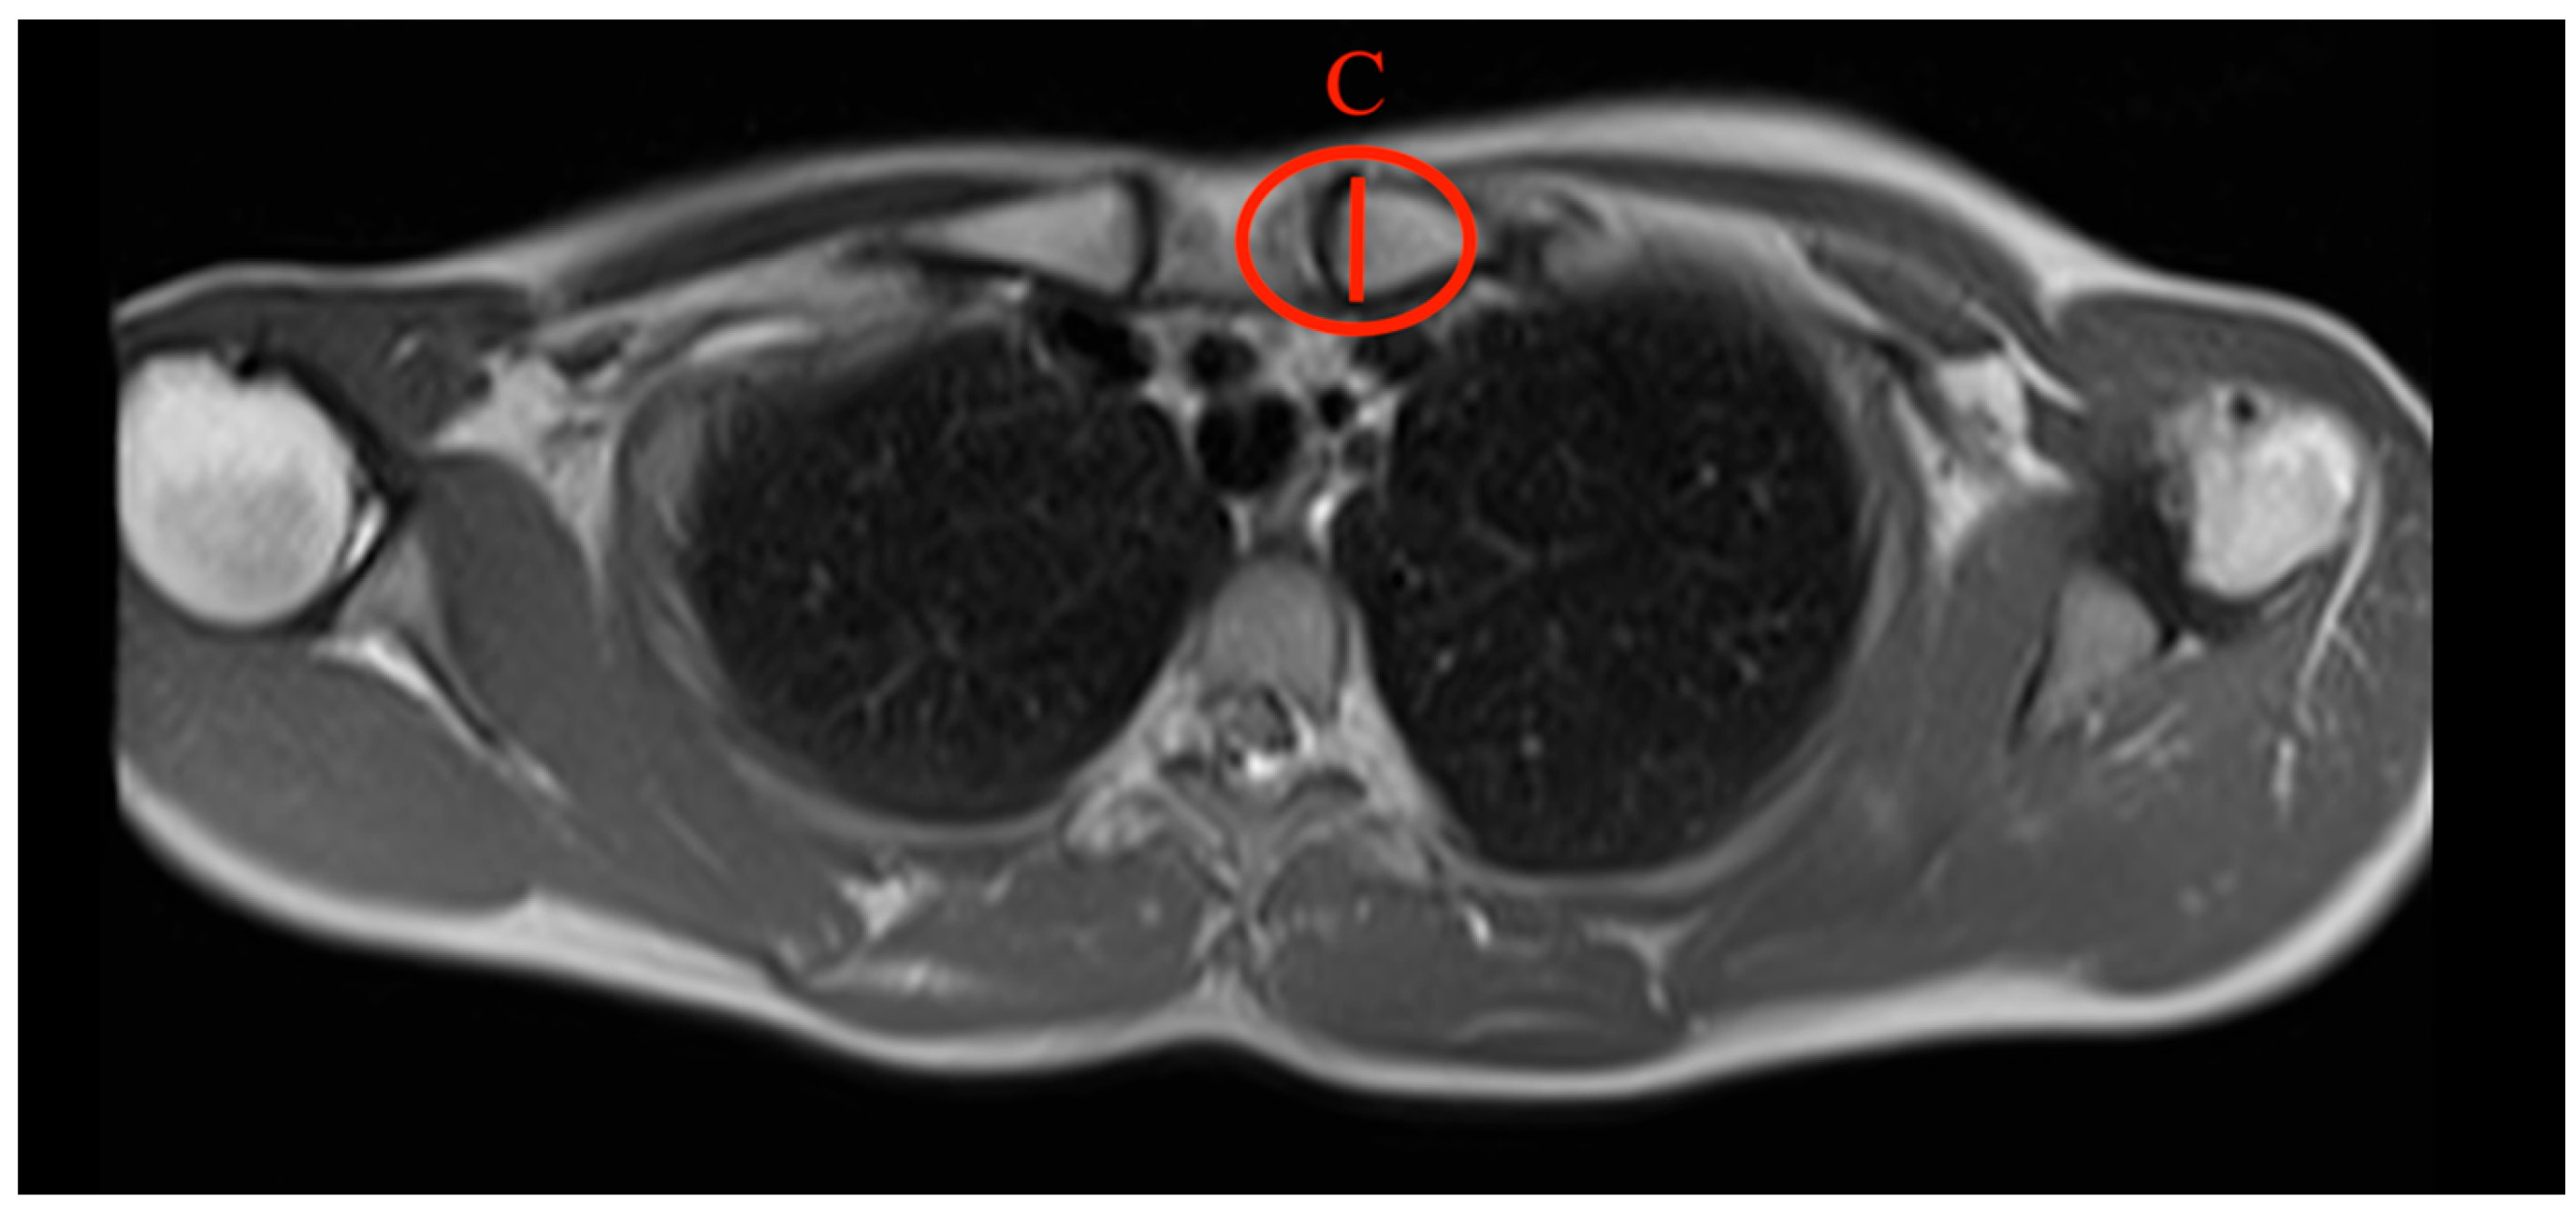

- Sternal angle: The sternal angle alpha was measured by the plug-in after the two tangents were drawn. Tangent 1 aligns at the sternal articular surface of the sternoclavicular joint, and tangent 2 is at the cranial end of the manubrium (Figure 1).